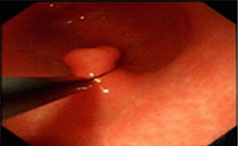

一般来说胃息肉的患者没有太多典型的症状表现,但是随着疾病的逐步发展或严重,胃息肉的患者可能会出现食欲减退、消化不良、胃部疼痛、恶心呕吐、腹胀......【详情】

常见症状:上腹隐痛、腹胀、不适

无痛性便血、脱垂

胃肠息肉的危害有哪些?

胃息肉可以引起上腹部的不适、消化不良、消瘦等,严重的可能引起癌变...【详情】